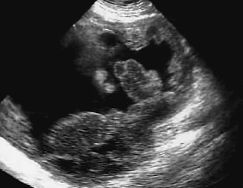

Tumor estromal borderline del estómago: diagnóstico por imagen en ecografía y TC

Los tumores estromales gastrointestinales (TEGI) son un tipo de tumores estromales no diferenciados cuyo desarrollo diagnóstico ha aumentado recientemente debido a las nuevas técnicas inmunohistoquímicas. Su principal característica, imprescindible para el diagnóstico de certeza, es que presentan células que inmunohistoquímicamente son positivas para el marcador específico CD34. Presentamos un caso de TEGI de malignidad borderline, que dependía de la pared externa del estómago y describimos sus características por imagen en ecografía y TC y su correlación anatomopatológica.

Gastrointestinal stromal tumors (GIST) are a type of undifferentiated stromal tumor that is recently being diagnosed more frequently owing to the introduction of new immunohistochemical techniques. Their main feature, indispensable for the definitive diagnosis, is immunohistochemical evidence of the presence of CD34-positive cells. We present a case of GIST of borderline malignancy involving the outer wall of the stomach, describing the ultrasound and computed tomography images and their correlation with the pathological features.